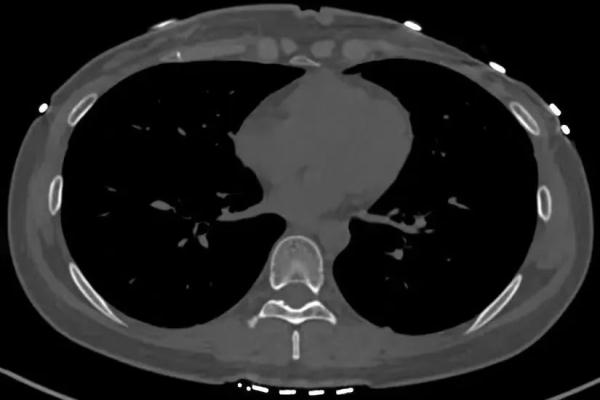

完善肋骨CT三维重建后,清晰提示左侧第6肋骨折。询问得知,杨女士经常出门过度防晒,长期接触不到光照。医生称,发生肋骨骨折的患者通常是有长期或剧烈的咳嗽史,伴随本身的骨质疏松或转移性骨肿瘤等病症。建议杨女士完善检查,明确是否有骨质疏松。